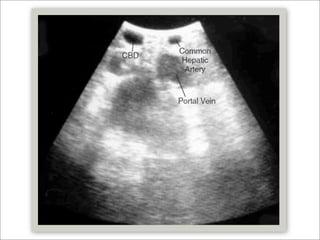

   Ultrasonido transabdominal

   Sensibilidad 0.3 – Especificidad 1.00

Generalidades  Diagnóstico y preoperatorio  Sospecha  PFH’s elevadas  Ictericia  Pancreatitis biliar  Signos radiológicos  Ultrasonido transabdominal  Sensibilidad 0.3 – Especificidad 1.00  TAC  Sensibilidad 65 - 93%  Especificidad 84 – 100%  Trondsen Prediction of common bile duct stones prior to cholecystectomy. Arch Surg 1998; 133:162–6.